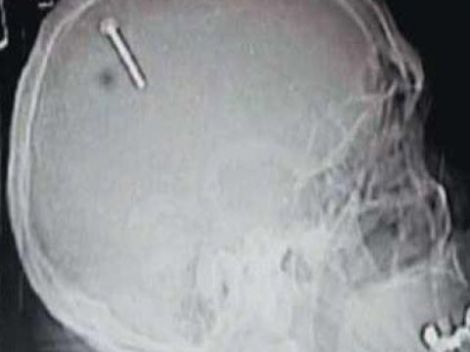

Brutalni samomor: Beograjčanka si je s kladivom v glavo zabila žebelj!